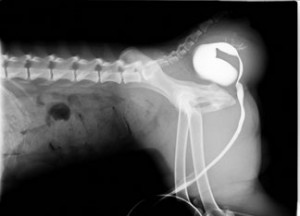

来院時、肛門右脇が大きくふくれており、レントゲン検査にて膀胱が反転してヘルニア嚢に嵌頓しておりかなり重度の状態でした。

来院時レントゲン検査:重度の便秘および膀胱の反転が認められました。

肛門右側の重度の会陰ヘルニアが認められます。